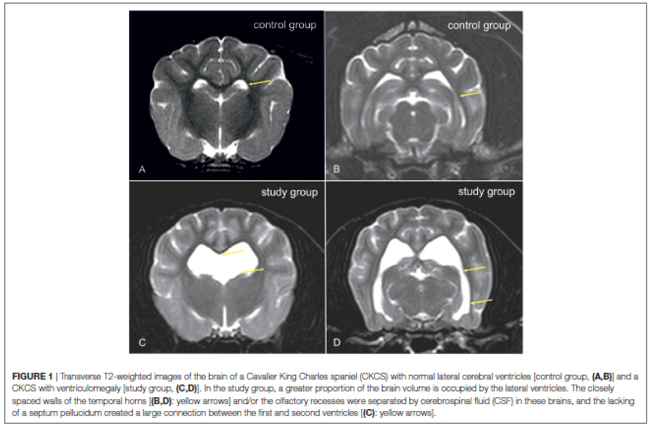

Below is a comparison between a canine brain with normal lateral cerebral ventricles (A) and one with enlarged lateral ventricles (B). From a May 2015 study led by Dr. Martin J. Schmidt.

Dynamic Susceptibility Contrast Perfusion Magnetic Resonance Imaging Demonstrates Reduced Periventricular Cerebral Blood Flow in Dogs with Ventriculomegaly. Martin J. Schmidt, Malgorzata Kolecka, Robert Kirberger, Antje Hartmann. Vet. Neuro. & Neurosurgery. August 2017; doi: 10.3389/fvets.2017.00137. Quote: The nature of ventriculomegaly in dogs is still a matter of debate. Signs of increased intraventricular pressure and atrophy of the cerebral white matter have been found in dogs with ventriculomegaly, which would imply increased intraventricular pressure and, therefore, a pathological condition, i.e., to some extent. Reduced periventricular blood flow was found in people with high elevated intraventricular pressure. The aim of this study was to compare periventricular brain perfusion in dogs with and without ventriculomegaly using perfusion weighted-magnetic-resonance-imaging to clarify as to whether ventriculomegaly might be associated with an increase in intraventricular pressure. Perfusion was measured in 32 Cavalier King Charles spaniels (CKCS) with ventriculomegaly, 10 CKCSs were examined as a control group. ... The presence of ventriculomegaly was based on the following criteria. Dogs with a normal ventricular system have very narrow and slit-like horns of the lateral ventricles. In the finding of ventriculomegaly, the interpreter subjectively noted a greater proportion of the intracranial volume occupied by the lateral ventricles. The closely spaced walls of the temporal horns and/ or the olfactory recesses were separated by cerebrospinal fluid (Figures 1C,D: yellow arrows) in these brains and the lacking of a septum pellucidum created a large connection between the first and second ventricles (Figures 1C,D: blue arrows). CKCSs without these findings were used as a control (Figures 1A,B). ... Cerebral blood flow (CBF) was measured using free-hand regions of interest (ROI) in five brain regions: periventricular white matter, caudate nucleus, parietal cortex, hippocampus, and thalamus. CBF was significantly lower in the periventricular white matter of the dogs with ventriculomegaly but not in the other ROIs. Reduction of periventricular CBF might imply increase of intraventricular pressure in ventriculomegaly. ... Cerebral blood flow can be reduced in periventricular white matter in CKCSs with ventriculomegaly, which makes some increase of intraventricular pressure likely.